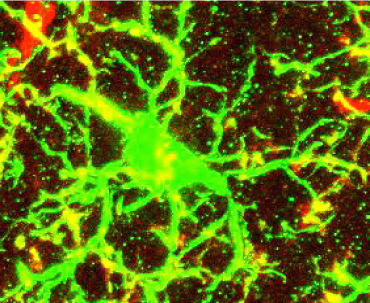

RIDE THE WAVES Compared with a mouse that received random brain stimulation (right), a mouse stimulated to produce more gamma waves (left) had less amyloid-beta (green) in its hippocampus.

H.F. Iaccarino et al/Nature 2016